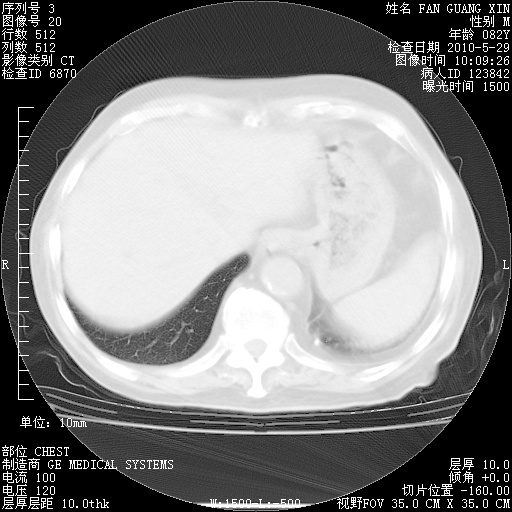

再治疗10天后的肺部CT 纵膈窗

阅读此次胸部CT,肺间质渗出性改变较入院时有吸收。目前从体温、白细胞、中性分叶明显增高,肯定存在细菌感染(发生医院感染哦,若无消化道及泌尿系统等感染的依据,肺部感染可能大)。若你院头孢哌酮舒巴坦钠耐药率较高,同意你的方案,若48小时体温仍高,可考虑使用碳青霉稀类抗菌药物,同时可予超声雾化、注意滴数时加大液体量。白蛋白33.30g/L较低哦,需加强营养等支持治疗。